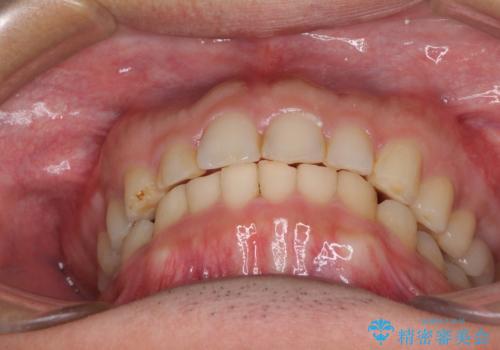

- 深い咬み合わせと前歯のデコボコ、奥歯の欠損を気にして来院された患者様です。

歯列矯正はインビザラインを使用し、矯正治療中の適切な時期に奥歯の欠損部位にインプラントを埋入することとしました。

矯正治療とインプラント治療を同じ歯科医師が担当することで、通常見られるような複数医院を行き来する煩雑さや、複数担当医の見解の違いによる治療の遅滞といった煩わしさは一切なく、スムーズに治療を進めることができました。

安定して咬めるようになり、患者様には大変満足していただきました。